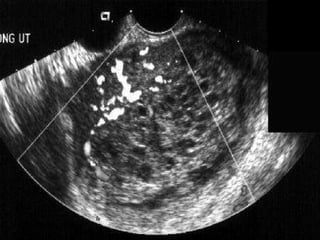

(4)  imaging : a- plain X-ray chest: may show secondaries in the form of &quot; cannon balls&quot; or &quot;snowstorm&quot; appearance. b- ultrasonography: to detect tumour, cystic ovaries and exclude remnants of conception. c- CT scan: for lungs, liver, brain and bone. (5) lumbar puncture : plasma hCG/ CSF hCG ratio less than 60 strongly CNS involvement my metastases  (6) blood studies : a- complete blood picture including platelet count  b- Renal, liver and thyroid function tests  c- Blood group.

(4) imaging: a- plain X-ray chest: may show secondaries in the form of &quot; cannon balls&quot; or &quot;snowstorm&quot; appearance. b- ultrasonography: to detect tumour, cystic ovaries and exclude remnants of conception. c- CT scan: for lungs, liver, brain and bone. (5) lumbar puncture : plasma hCG/ CSF hCG ratio less than 60 strongly CNS involvement my metastases (6) blood studies : a- complete blood picture including platelet count b- Renal, liver and thyroid function tests c- Blood group.